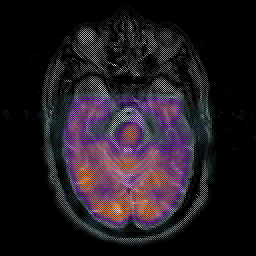

Subacute Stroke overlay -- Slice #7

[Home][Help][Clinical] Slice 7